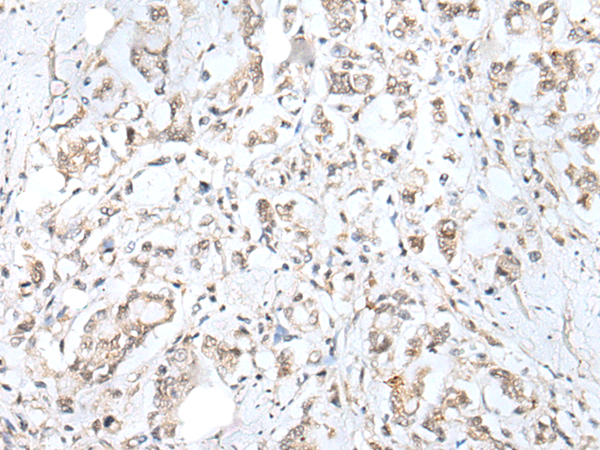

IHC positive control:

Human brain and human gastric cancer